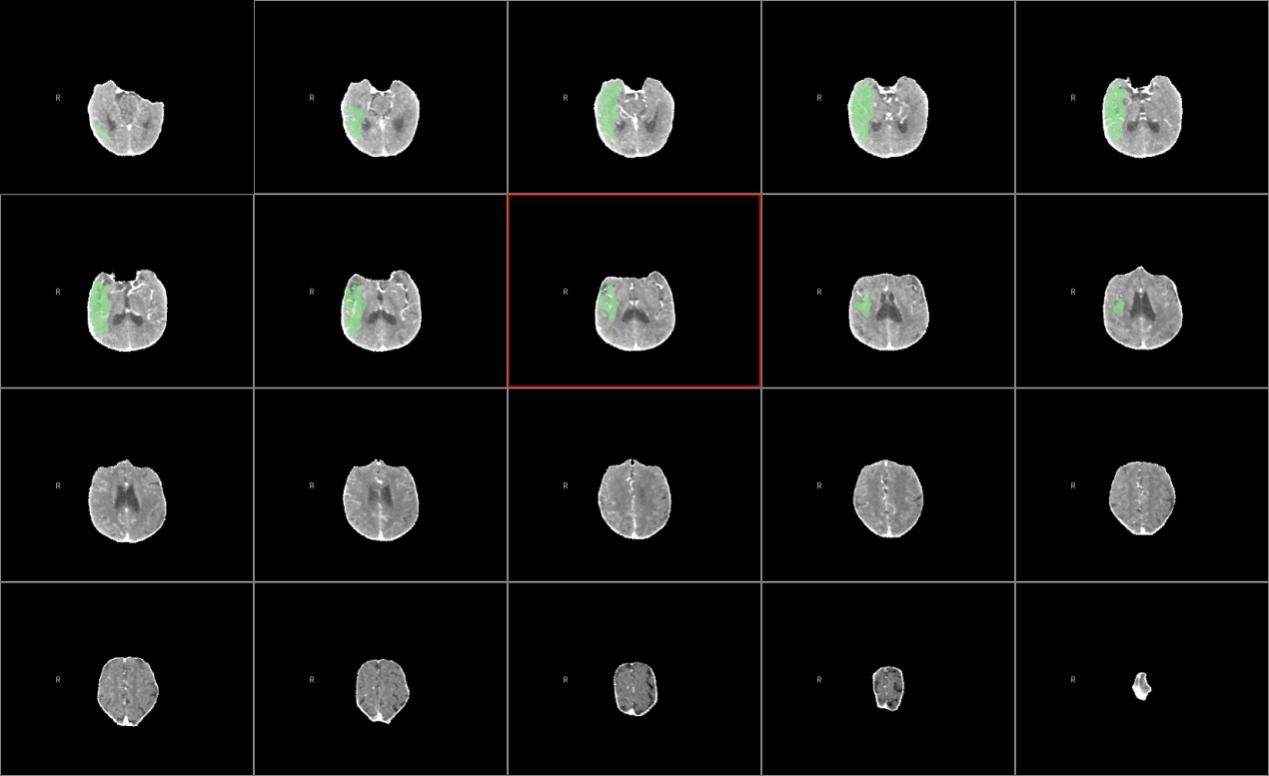

CTP提示右侧大脑半球存在大片缺血半暗带